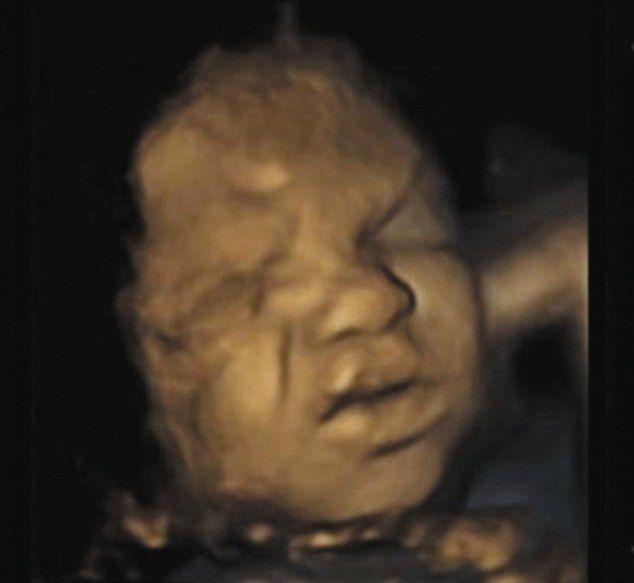

Υπερηχογραφήματα που μελετήθηκαν από επιστήμονες απεικονίζουν μωρά στην κοιλιά της μαμάς τους να παίρνουν εκφράσεις σαν να πονάνε.

Ανασηκώνουν τα βλέφαρά τους, σουφρώνουν τη μύτη τους και ανοίγουν διάπλατα το στόμα τους σαν να θέλουν να μιλήσουν. Στις περισσότερες τρισδιάστατες εικόνες πάντως, οι εκφράσεις τους είναι αυτές του πόνου, του θυμού, της έντασης. Και γι' αυτό οι ειδικοί επιμένουν πως τα αγέννητα μωρά δεν κάνουν τίποτα άλλο από το να προετοιμάζουν το πρόσωπό τους για τις αντιδράσεις που θα έχουν όταν θα ζήσουν στον πραγματικό κόσμο που είναι γεμάτος δυσκολίες και προβλήματα. Οι Βρετανοί γιατροί έχουν αντίθετη άποψη όμως. Ο Δόκτωρ Ρέισλαντ λέει μεταξύ άλλων: «Η έρευνά μας υποδεικνύει ότι οι εκφράσεις στο πρόσωπο και οι κινήσεις των μυών των μωρών εντάσσονται στη διαδικασία ανάπτυξής τους και δεν έχει σε καμία περίπτωση να κάνει με συναισθήματα». Όπως και να έχει, οι 4D φωτογραφίες των μωρών μέσα στην κοιλιά, επιτρέπουν στη μέλλουσα μαμά να έχει μία καλή εικόνα των χαρακτηριστικών του μωρού της που είναι... αξία ανεκτίμητη!